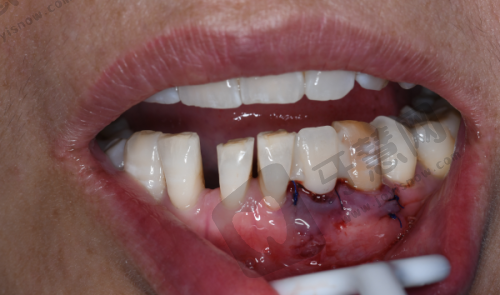

在泉州安格尔口腔开展美国百康种植牙7800元起项目的医生们,具备丰富临床经验和专精知识。他们经过系统口腔医学培训,对种植牙技术有深入研究和掌握。面对患者,医生会详细检查和评估口腔、身体状况及需求,制定个性化种植方案。例如对于骨量不足的患者,采用骨增量技术创造良好条件。种植过程中操作精细,严格遵循手术规范,确保种植体正确植入,密切关注患者反应并及时处理问题。术后还会为患者提供详细护理指导,如告知饮食注意事项,避免食用实力强、过烫食物,保持口腔清洁等。凭借专精技术和负责态度,医生们让泉州安格尔口腔的美国百康种植牙项目得到众多患者认可,帮助患者解决牙齿缺失问题,重新拥有健康美丽的牙齿。